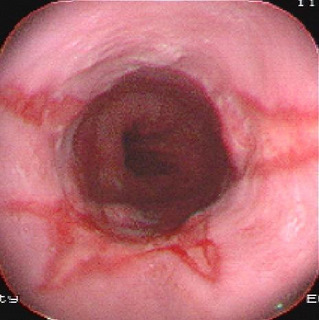

食管癌是常見的消化道腫瘤,全世界每年約有30萬人死于食管癌。其發(fā)病率和死亡率各國差異很大。我國是世界上食管癌高發(fā)地區(qū)之一,每年平均病死約15萬人。男多于女,發(fā)病年齡多在40歲以上...

食管癌發(fā)生于世界各國,其高發(fā)區(qū)有顯著的地理性差異。2000多年以前中國豫西一帶已有噎膈的記載。多數(shù)學(xué)者認(rèn)為食管癌是由環(huán)境中的致癌因素引起。已提出的致癌因素包括亞硝胺類化合物和...